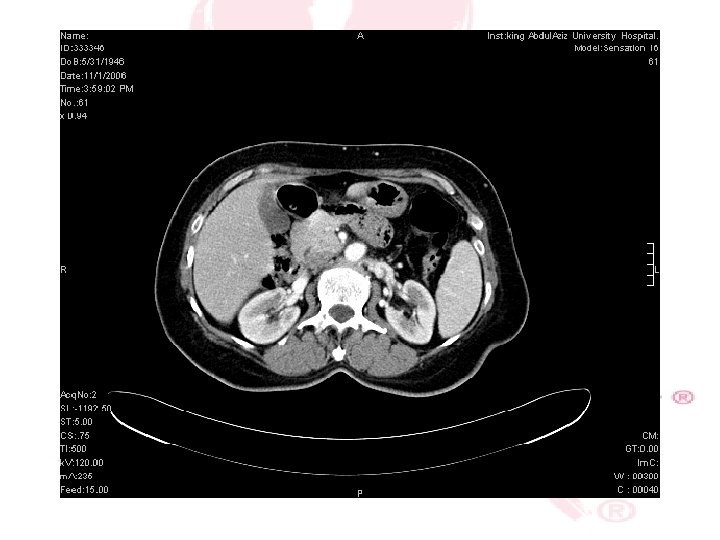

CT SCAN CHEST , ABDOMEN &PELVIS